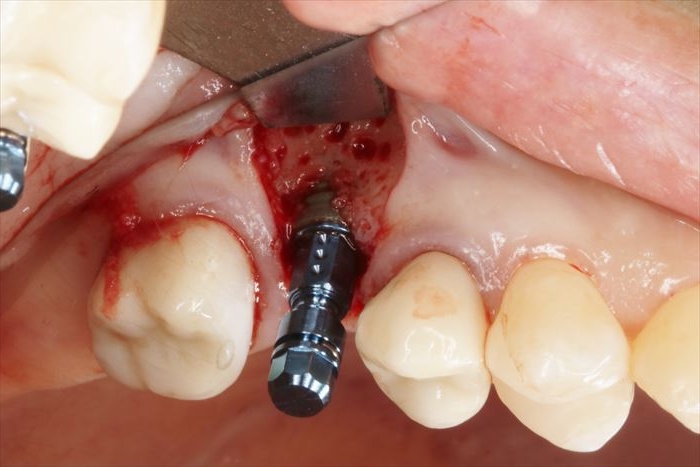

スイス ストローマン社製のインプラントを用います。

BLT Roxolid φ4.1㎜ 長さ8㎜

インプラントの埋入を終えました。

インプラントを植えるためのパーツである挿入ジグを外しました。

ここから骨増生処置に移ります。